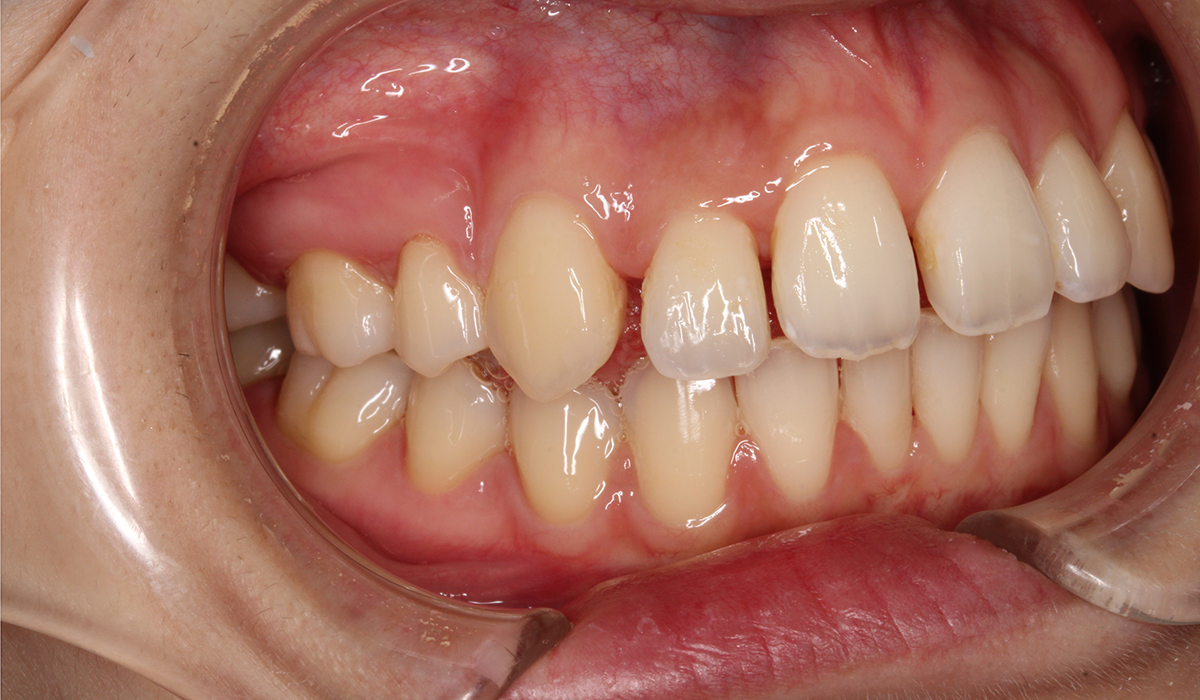

今回ご紹介する患者様は、全体的な歯のガタツキを気にされており、矯正検査後叢生Ⅰ級と診断いたしました。

左側

術前

BK終了時

術後